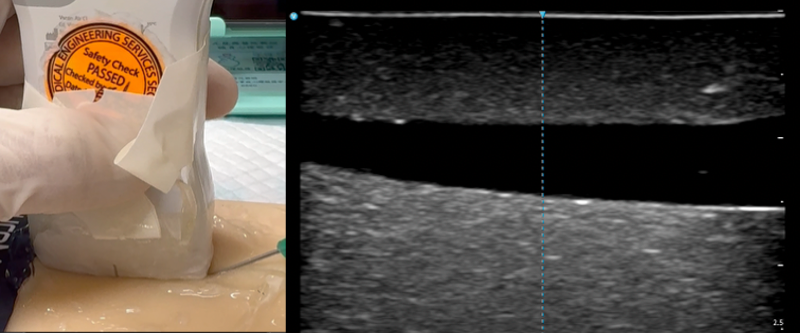

🚅Long Axis Approach

The long axis approach is also called the in-plane or longitudinal approach. As the name implies, the structures are all in-plane with the ultrasound beam. This approach is technically more demanding since one had to cut both the vessel and the fine needle along their long axis with one plane of narrow ultrasound beam. Contrary to the short axis approach, only the needle moves while the probe should remain stationary throughout the insertion. Therefore, the initial placement of the probe to obtain an optimal long axis view is crucial. This approach require precise movements and excellent hand-eye coordination. You should begin with short axis approach first. Advance to practising long axis approach only when you are comfortable with short axis.

- Insert the needle and advance slowly

- Tent and pop the vessel wall

- Verification: Connect the catheter to saline lock. Perform a 10 mL saline flush to confirm the patency. Low resistance flushing and lack of tissue swelling is an indication of successful placement. Alternatively, you may visualse the whole catheter within lumen using long axis view. You may also see the snowstorm of bubbles using POCUS while flushing saline.